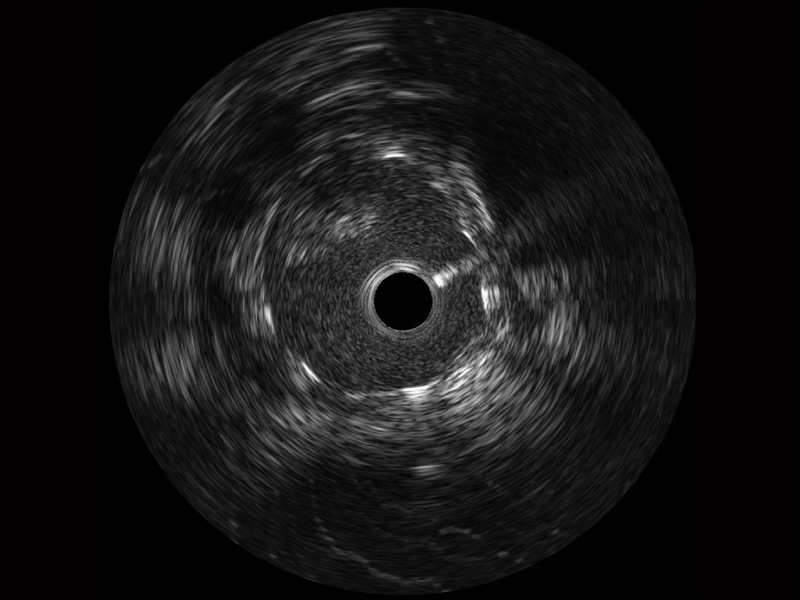

传统IVUS图像

对比传统IVUS导管成像,百老汇电子游戏官网宽频IVUS图像的近场支架梁显影更细腻,远场中膜外血管仍清晰可辨,兼顾远中近,兼顾分辨力与穿透深度